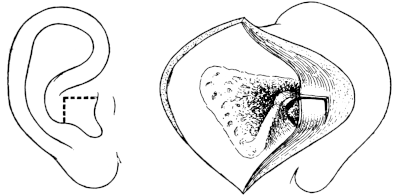

| 210. | Passing the Eustachian Catheter | 365 |

| 211. | Passing the Eustachian Catheter | 365 |

| 212. | Passing the Eustachian Catheter | 366 |

| 213. | Passing the Eustachian Catheter | 366 |